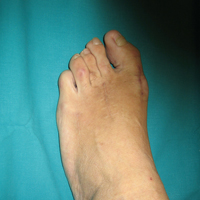

• Κότσια - Εξαρθρήματα μεταταρσίων